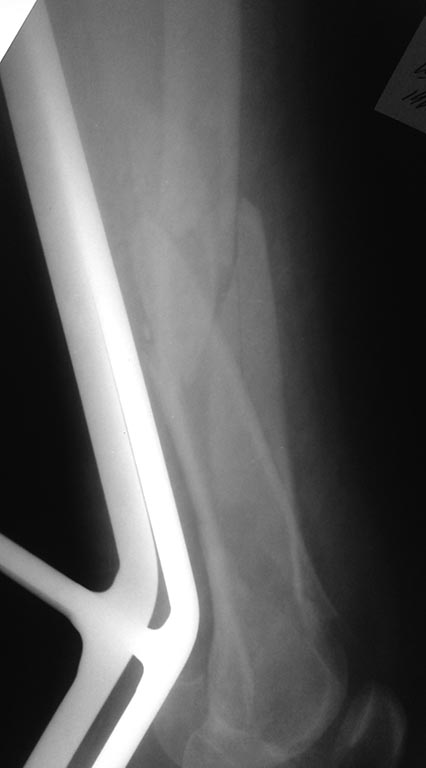

Re: Перелом бедра

Артротомию и репозиция деафиза лучше делать одномоментно ч\з один доступ?